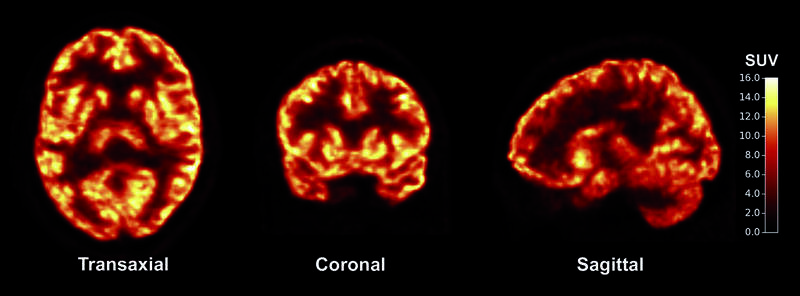

波士顿大学神经科学家罗伯特莱恩哈特进行的这项研究,对150名65岁到88岁的人做实验,其中一组人接受高频60赫兹的gamma波刺激前额叶皮质,这个区域与语言、高层次认知功能有关;第二组人接受低频4赫兹的theta波刺激在学习、记忆功能扮演重要角色的顶叶皮层;第三组为对照组。

受试者每天接受20分钟电流刺激,连续进行4天,并且做5回合20个单字记忆测验,每次测验结束后立即回忆测验中的单字。研究人员用两种方式评估记忆力:从单字表最后单字往前回想,因为后面的单字才刚听到,可测验短期或称工作记忆力;第二种是从单字表前面的单字开始回想,由于听到前面的单字的时间已经过了一会,可评估稍微长期的记忆力。

这份研究报告在《自然神经科学杂志》上发表。研究人员也测试将两种电流波长对调,即改以高频gamma波刺激顶叶皮层、用低频theta波刺激前额叶皮质,但是都跟对照组一样,记忆力未见改善。